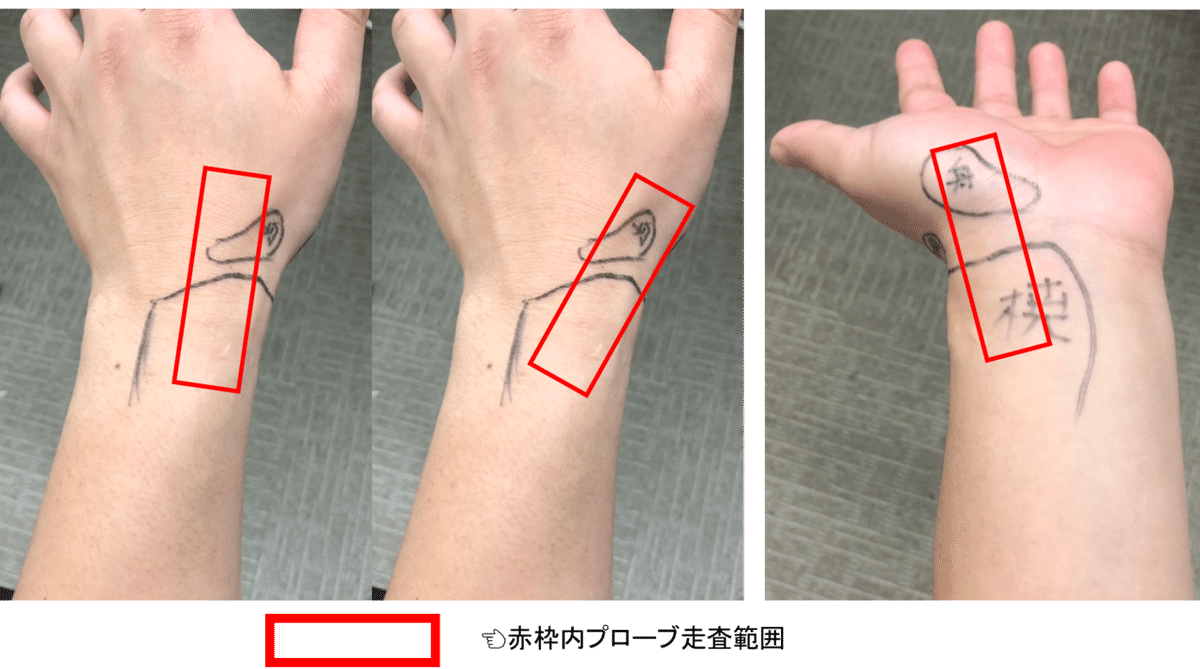

観察方法

舟状骨は背側,外側,掌側

3方向から観察でき

微細な骨折であっても

そのほとんどに対応することができます

一番スタンダードで観察しやすい

掌側走査 長軸の観察法を紹介します

コツとしては

中央の特徴的なS字のラインを描出してください